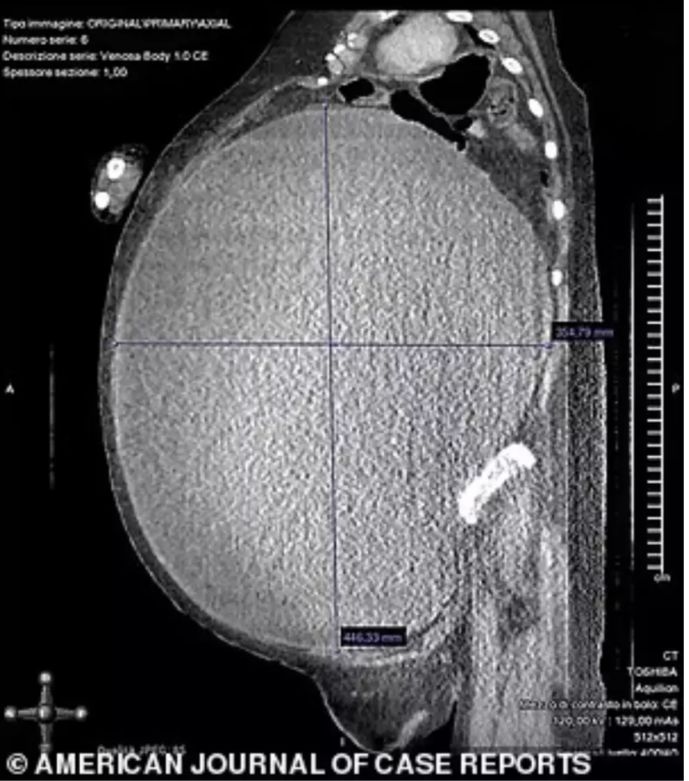

De acordo com a publicação, o procedimento demorou cerca de seis horas e meia e foi considerado de alto risco. O cisto estava no ovário direito e tinha 40 centímetros de comprimento.

Antes da cirurgia, a italiana estava com o abdômen "extremamente inchado", além de sentir refluxo. Ela também tinha dificuldades para se locomover e para respirar. Um ultrassom mostrou que sua cavidade abdominal estava totalmente ocupada por lesões.

Durante o procedimento, os médicos precisaram drenar 37 litros de líquido antes de remover o útero e os ovários e a mulher precisou receber algumas transfusões de sangue. Após a cirurgia, ela ainda ficou na UTI por 30 dias e teve parada cardíaca e insuficiência renal aguda, mas conseguiu se recuperar e deixou o hospital depois de dois meses.

Os médicos continuaram acompanhando o caso dela e, após dois anos, informaram que ela "está completamente recuperada e livre de doenças". Antes da cirurgia, a italiana pesava 123 quilos e tinha um Índice de Massa Corporal (IMC) de 50,5 (considerada obesa mórbida). Depois do procedimento, seu IMC era de 28,3. O caso foi divulgado no jornal científico American Journal of Case Reports.